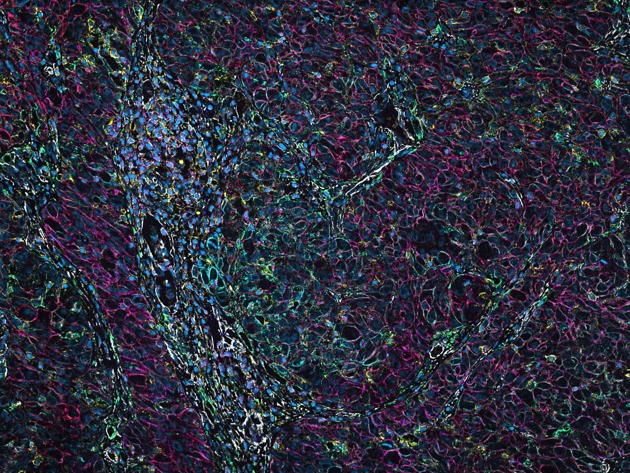

Runner-up Karen van der Sluis noemde haar winnende beeld Cancerous confetti (zie afbeelding). Ze doet promotieonderzoek bij de afdelingen pathologie en chirurgie en maakte het beeld voor een onderzoek naar hoe de micro-omgeving van een slokdarmtumor de ontwikkeling van de kanker beïnvloedt. “Om meer te weten te komen over de evolutie die een slokdarmtumor doormaakt bestuderen we het genoom van de tumor, voor en na behandeling en wanneer de ziekte terugkomt. Daarnaast kijken we naar de micro-omgeving van de tumor en of deze invloed heeft op welke cellen overleven. We hebben dit bekeken door afweercellen en tumorcellen te kleuren met immunofluorescentie, wat prachtige plaatjes opleverde.”

Cancerous confetti

100 verschillende eiwitten

De derde plaats gaat naar Cellulaire caleidoscoop gemaakt door analist Iris Seignette van de afdeling Pathologie, begeleid door Erik Hooijberg en Gerrit Meijer. “Een kwaadaardige tumor bestaat niet alleen uit kankercellen, maar ook uit veel andere cellen zoals structuurcellen en cellen van het immuunsysteem”, zegt Iris, die onderzoekers ondersteunt en traint in beeldanalyse. “Het is van groot belang om te onderzoeken hoe al deze cellen zich gedragen en met elkaar communiceren. Onder de microscoop kunnen we dit visualiseren dankzij kunstmatige kleuren die we aan eiwitten hangen. Tot voor kort konden we zes tot acht eiwitten tegelijk in beeld brengen, maar met de nieuwe CODEX-technologie kunnen we tot 100 verschillende eiwitten kleuren in één enkel weefselplakje van ongeveer 3 micrometer dun. Deze technologie biedt zoveel meer context."